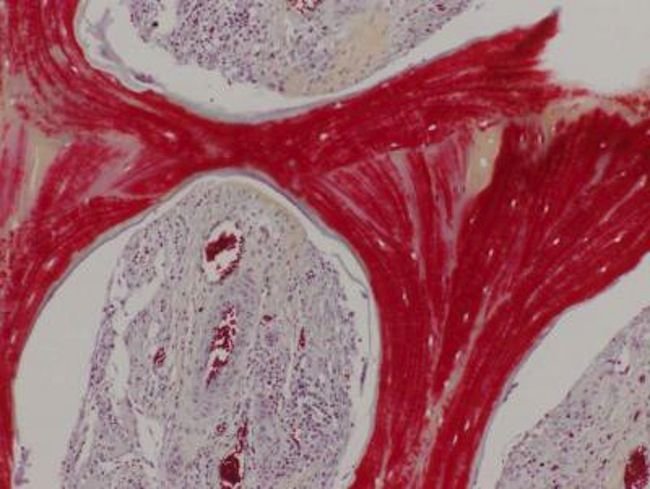

محققان ابتدا سلولهای بخشهایی از استخوان ران گاو را با استفاده از مواد شوینده و آنزیم حذف کرده و تنها چارچوب آن را نگهداشتند. سپس این چارچوبها به شکل واحد راموس-کندیل آرواره خوکها قالبگیری شدند.

در مرحله بعد به این چارچوبها سلولبنیادی خوکها اضافه شد و درون راکتورهای زیستی قرار گرفت تا اکسیژن و مواد مغذی سلولها را تامین کنند. پس از چند هفته این سلولها به استخوان نیمه بالغ زنده تبدیل شدند.